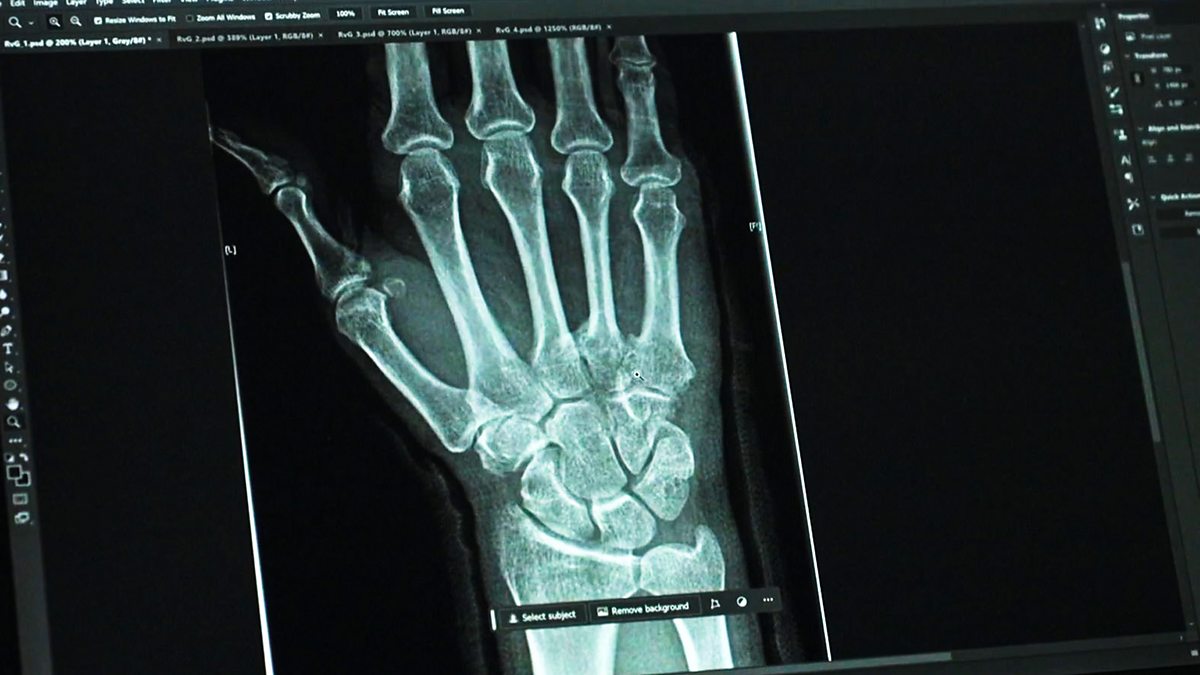

When a disabled woman is found brutally murdered in her home, her neighbour is the prime suspect. Rhona Heywood was found dead next to her unconscious neighbour in 2008 after spending an evening drinking together. Martin Garratty claimed he had been asleep and had no recollection of murdering Rhona, but injuries to his face and hands, consistent with an attack, were enough to charge him with murder. At the trial, questions arose as to the nature of one of his injuries, a broken finger, suggesting it had occurred prior to Rhona’s murder. As a result, the prosecution's case was put under scrutiny. A consultant doctor, Rowley Cottingham, was brought in to prove without a doubt that other injuries found on his face and hands were in fact made by his violent and deadly attack on Rhona.